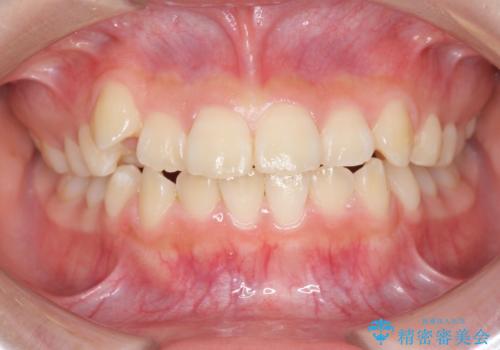

インビザラインで行う八重歯の治療

- 笑った時に目立つ八重歯の矯正治療を求めて来院されました。

マイクロインプラントを用いた臼歯の後方牽引、およびゴムかけ等の付加処置を駆使して八重歯の治療を行っていきます。